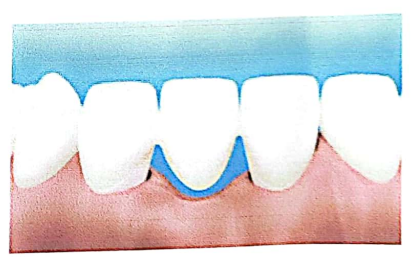

4. L’espace biologique : Espace de 2mm entre le fond du sulcus et le sommet de la crête osseuse alvéolaire. Zone interdite à la limite prothétique.

La limite cervicale peut être :

- Supra-gingivale

- Juxta-gingivale

- Intra-sulculaire

- Respect de l’espace biologique

- Éviter une limite de préparation dans l’espace biologique. Si le bord de la reconstruction est placé à l’intérieur de « l’espace biologique », l’inflammation et l’activité ostéoclastique seront stimulées.